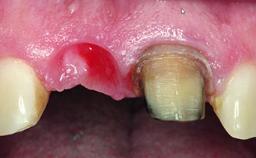

In 2008, a healthy 15-year-old female, non-smoking patient presented at our clinic with a major esthetic problem of tooth 21. Her dental history revealed that the tooth had been avulsed by trauma years before. As a result, the replanted and temporarily splinted tooth had ankylosed and was in severe apical malposition. The ankylosed tooth exhibited a significant gingival recession that disturbed the patient greatly. Due to the patient’s low age and with her skeletal growth not completed, periodic follow-up visits were scheduled to monitor the situation until the patient was old enough for implant therapy.